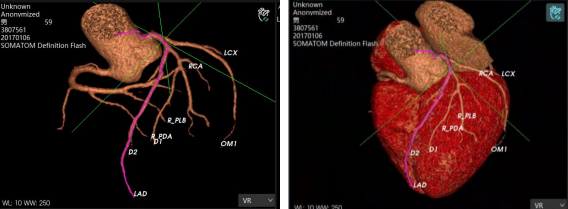

AI智能影像輔助診斷技術(shù)具有對(duì)醫(yī)學(xué)影像進(jìn)行圖像篩查、病灶分類(lèi)、定位、檢測(cè)、圖像分割等優(yōu)勢(shì)。它能夠在海量的醫(yī)學(xué)影像中準(zhǔn)確、快速且客觀地篩選出特定疾病的影像,確定圖像中病變區(qū)域的空間位置,檢測(cè)需要識(shí)別圖像中所有的目標(biāo)并且確定其類(lèi)別,并在醫(yī)學(xué)影像中分割標(biāo)注出不同的組織和器官,計(jì)算圖像中的血流量等代謝信息。

除上述肺結(jié)節(jié)人工智能篩查示例外,目前已形成了全鏈路人工智能產(chǎn)品解決方案,在影像、超聲、病理方面都與AI智能影像輔助診斷技術(shù)高效結(jié)合,幫助醫(yī)院實(shí)現(xiàn)自動(dòng)化、高精度的影像診斷檢查,讓患者在疾病篩查中實(shí)現(xiàn)早期診斷、預(yù)測(cè)、治療、療效評(píng)估與監(jiān)測(cè)。